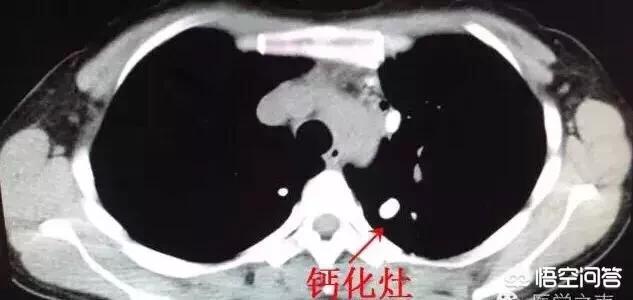

現在では、CT検査で肺に線維性病巣や石灰化病巣を見つけることは比較的日常的に行われている。 一般に、限局した筋状病巣や石灰化病巣は、その場所が古い病変であることを示しており、下図は左肺尖部に石灰化病巣を認めた患者の典型的なCT画像である。